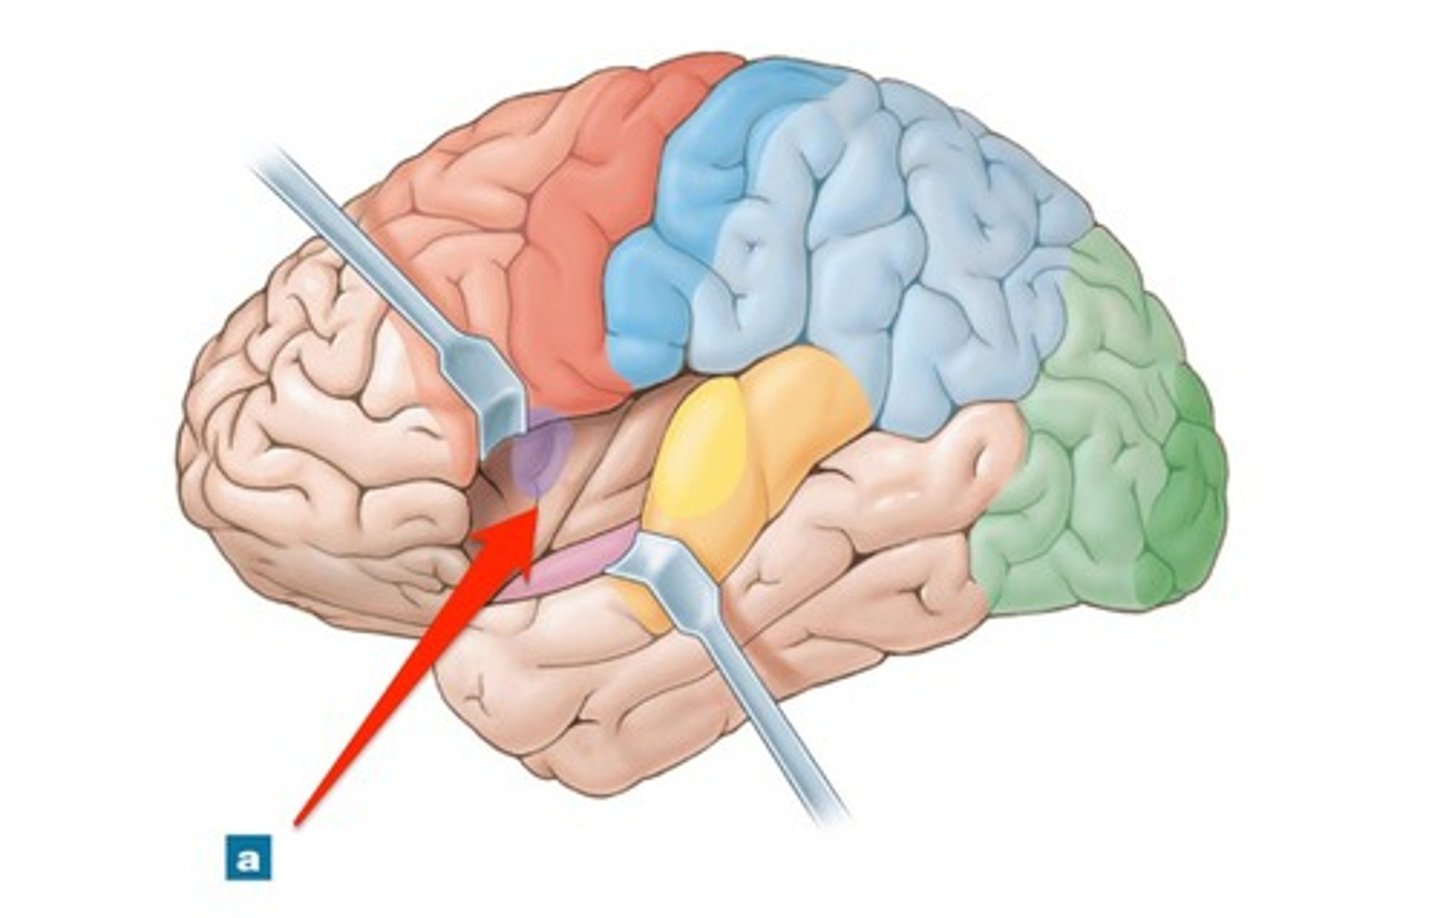

frontal lobe

parietal lobe

temporal lobe

occipital lobe

insula

lateral fissure

central sulcus